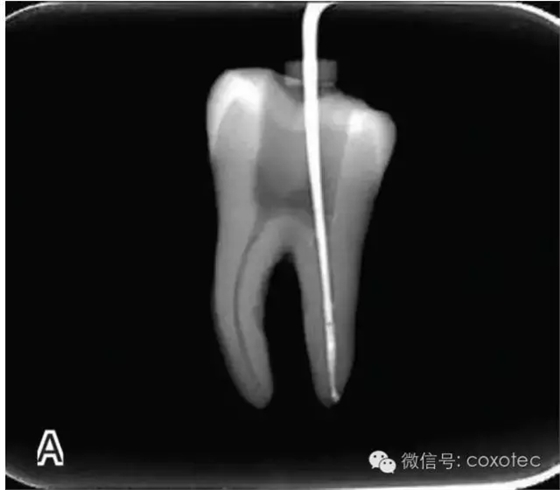

將主尖的尖1/3 部分蘸一薄層根充糊劑,緩慢插入根管內,并左右旋轉主尖,以將根充糊劑均勻涂布于根管壁上,如圖4所示。

圖4 放置主尖及糊劑,A.放置主尖及糊劑 B.X線片下示主尖及糊劑的放置